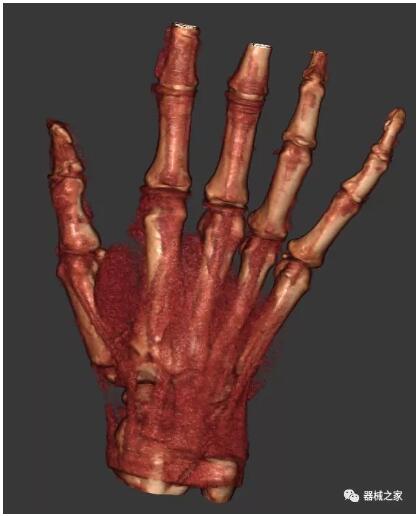

另外一款被稱為世界上最小的CT,它的重量僅300磅,不僅能夠掃查足部,還可以檢查膝蓋和上肢等。

這款CT使用非常方便,通過上下移動保持與患者的手臂或者雙腿齊平,掃描快速,僅需要30秒左右就可以完成掃查。

以上介紹的CT均來自國外同一家公司,這些CT均配置了可視化軟件,可以進(jìn)行切片、3D重建以及大型CT附帶的所有典型的操作功能。

以下是這些“特立獨(dú)行”的CT所拍出來的圖像: